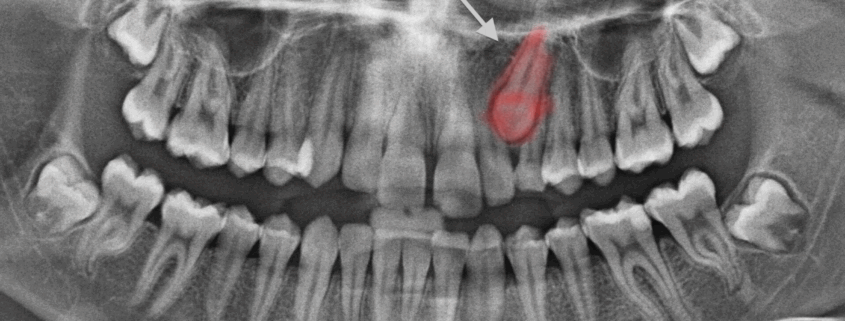

Une canine permanente (souvent supérieure) n’a pas fait son éruption normale.

Elle reste enfouie dans l’os ou sous la gencive, parfois mal orientée ou bloquée par d’autres dents.

Cela peut entraîner des complications : déplacement des autres dents, kyste, résorption radiculaire des dents voisines, asymétrie esthétique, etc.

Examen clinique + radiographie panoramique + scanner 3D si nécessaire.